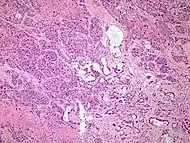

The most common form of pancreatic cancer (adenocarcinoma) is typically characterized by moderately to poorly differentiated glandular structures on microscopic examination. There is typically considerable desmoplasia or formation of a dense fibrous stroma or structural tissue consisting of a range of cell types (including myofibroblasts, macrophages, lymphocytes and mast cells) and deposited material (such as type I collagen and hyaluronic acid). This creates a tumor microenvironment that is short of blood vessels (hypovascular) and so of oxygen (tumor hypoxia).[2] It is thought that this prevents many chemotherapy drugs from reaching the tumor, as one factor making the cancer especially hard to treat.[2][3]

| Cancer type | Relative incidence[11] | Microscopy findings[11] | Micrograph | Immunohistochemistry markers[11] | Genetic alterations[11] |

|---|---|---|---|---|---|

| Pancreatic ductal adenocarcinoma (PDAC) | 90% | Glands and desmoplasia | ![]() |

|